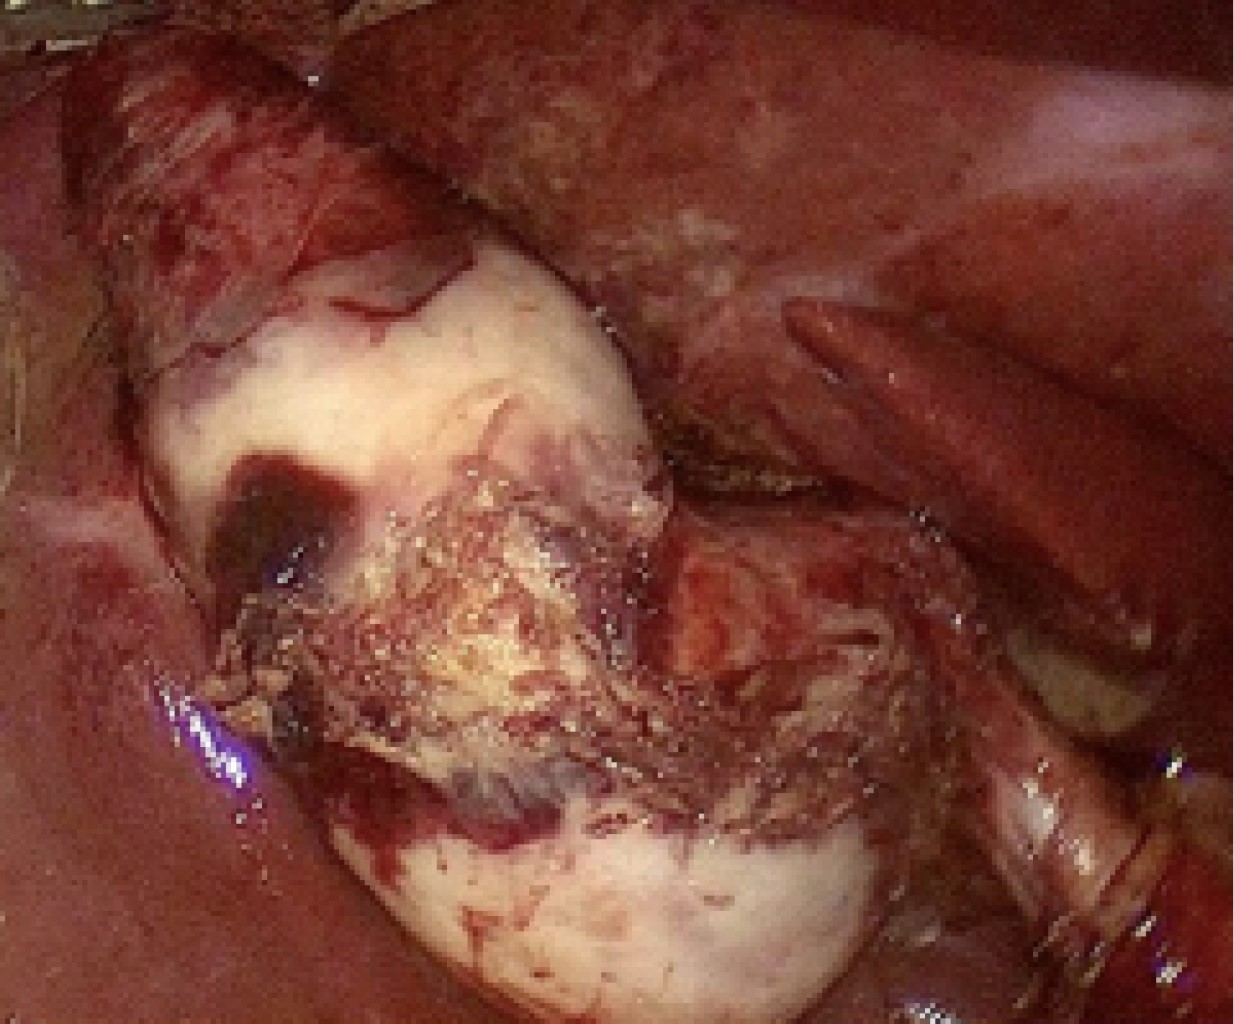

Introduction: the porcelain gallbladder represents a rare entity and it's associated with risk of malignancy. The treatment of choice is cholecystectomy, representing a surgical challenge given the degree of inflammation and fibrosis that this entity entails. Clinical case: we present a 56-year-old female with a history of recurrent episodes of biliary colic. She presents abdominal pain in the right hypochondrium of 7 hours of evolution, VNS (verbal numeric scale) 7/10 and nausea. Surgical treatment with laparoscopic cholecystectomy was decided. A gallbladder with a high degree of fibrosis, pearly color and adhesions to the omentum was found, a subtotal cholecystectomy was decided. Intraoperative retrograde cholangiography shows bile leakage from cystic duct and stent placement is performed. Conclusion: porcelain gallbladder is a histopathological condition in which there is calcification that infiltrates the gallbladder tissue. Found in 95% of cases of gallbladder lithiasis and represents special difficulty by limiting the field of vision due to its high degree of fibrosis. The prognosis depends on the degree of inflammation and the presence of malignancy. This entity entails a diagnostic and surgical challenge where the use of safe surgical alternatives for the patient becomes primordial, the technical knowledge and use of subtotal cholecystectomy is necessary for every surgeon who plans to perform laparoscopic cholecystectomy.

Figure 2